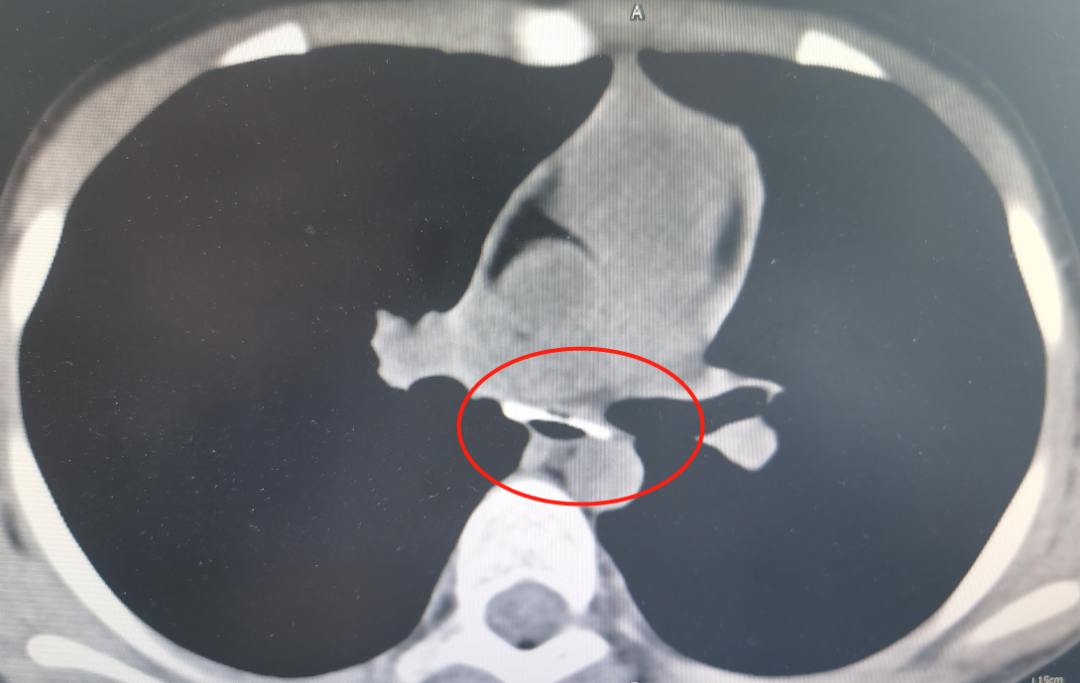

晚上7点左右,艳艳被送到了西南医科大学附属中医医院心胸外科,值班医生李亮接诊安排完善了相关检查,发现鸭骨位置极其特殊:前面是心脏,后面是胸主动脉,左右都是气管,鸭骨取出难度较大,稍不注意就可能划破食管,损伤其它器官组织。